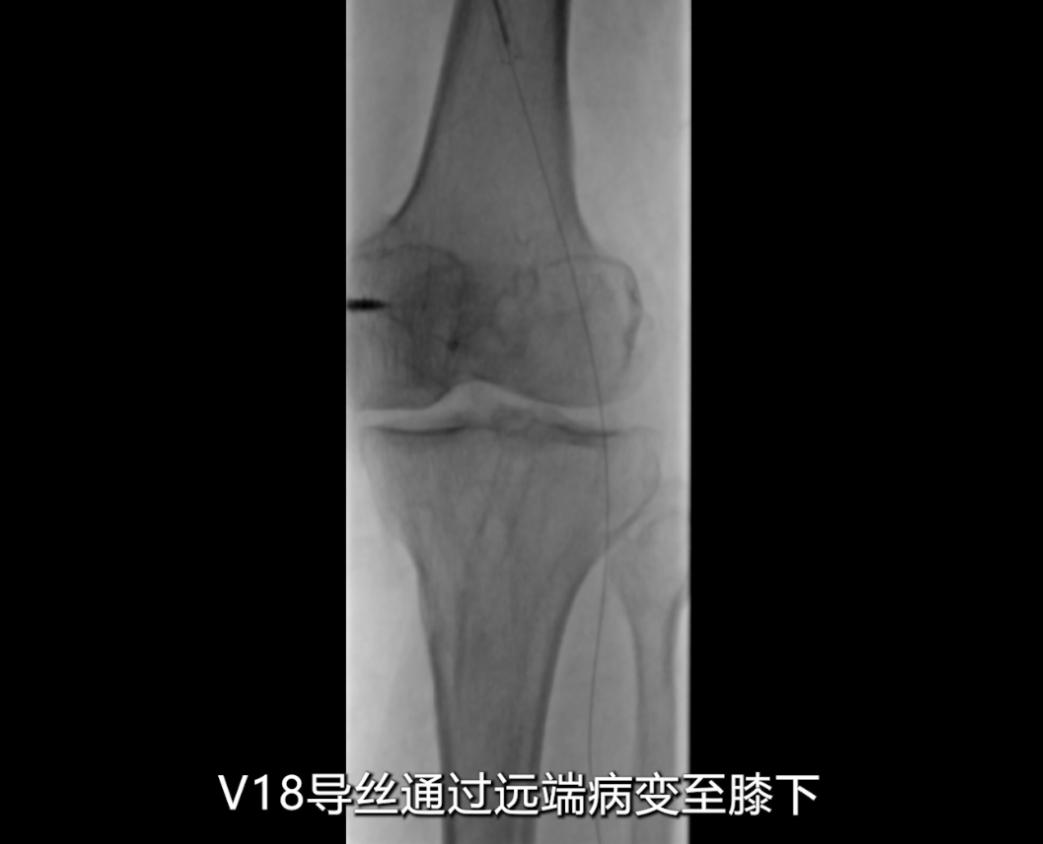

导丝通过闭塞段

采用单弯导管配合硬导丝及V18导丝,小心通过支架闭塞段,最终将V18导丝顺利送至膝下腓动脉段,未出现血管穿孔等并发症。